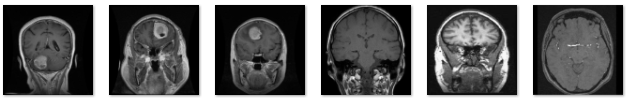

图4 数据集图片

本研究通过清洗与筛选原始脑部MRI影像数据,构建了一个包含“脑胶质瘤”、“脑膜瘤”、“垂体瘤”和“正常脑部”四种脑部状态的MRI影像数据集。数据集类别分布均衡,全面涵盖了不同类型的脑肿瘤及健康脑组织影像,所有样本均经过标准化处理与质量控制,确保影像的清晰度与代表性。该数据集为深度学习模型在脑肿瘤分类与诊断中的应用提供了坚实的数据支撑,为医学影像智能分析和脑部疾病的自动化诊断研究奠定了基础。